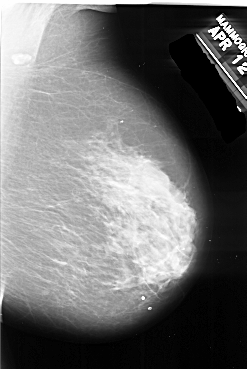

A_1017_1.RIGHT_MLO

RIGHT_MLO LINES 6271 PIXELS_PER_LINE 4186 BITS_PER_PIXEL 16 RESOLUTION 42 NON_OVERLAY